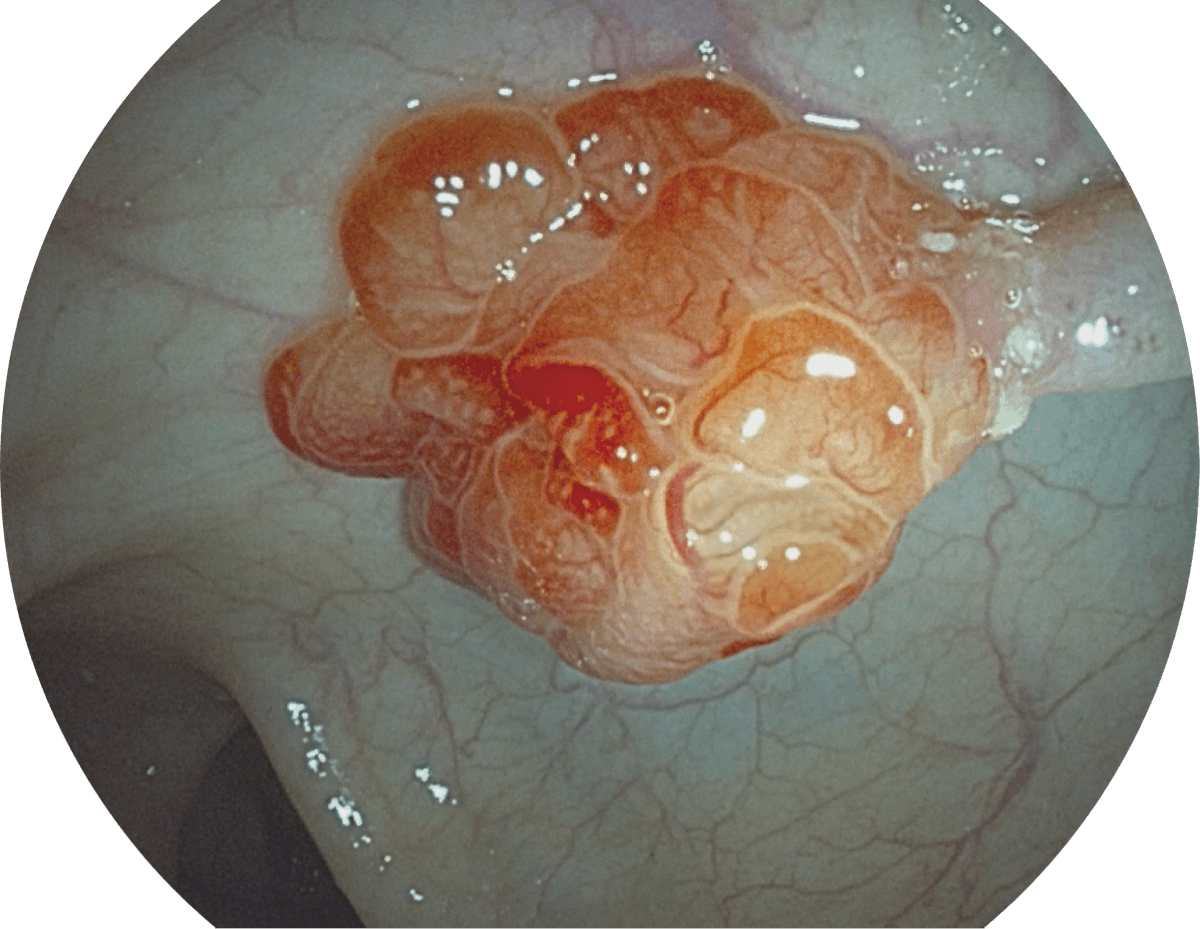

图像具有高亮度、高黏膜血管颜色对比度的特点,且不改变粘液、食物残渣、粪便的基本颜色,可在中远景下进行观察,助力消化道早期疾病的诊断。

• SFI